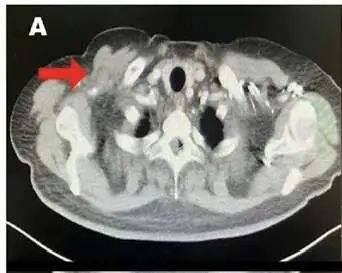

2016年11月(术后2年),在一次复查中发现“右锁骨下、锁骨上、右胸肌间淋巴结转移”。做穿刺活检确认性质,结果证实是乳腺癌复发。

图1 CT示术后锁骨下复发淋巴结

事已至此,怨天尤人没有用。我快速调整好心态后,主动和医生沟通了解接下来的治疗方案。医生的建议是行系统化疗+局部放疗+内分泌治疗方案。

随后,我接受了6个周期的化疗(多西他赛+卡培他滨),效果不错,肿瘤缩小了。

待身体恢复一段时间后,我继续投入接下来的治疗,对癌细胞乘胜追击。于是在2017年6-8月,我又做了局部放疗,靶向照射复发淋巴结区域(右胸壁+锁骨上下淋巴结)。放疗结束后,我改用依西美坦(一种芳香化酶抑制剂)进行内分泌治疗。